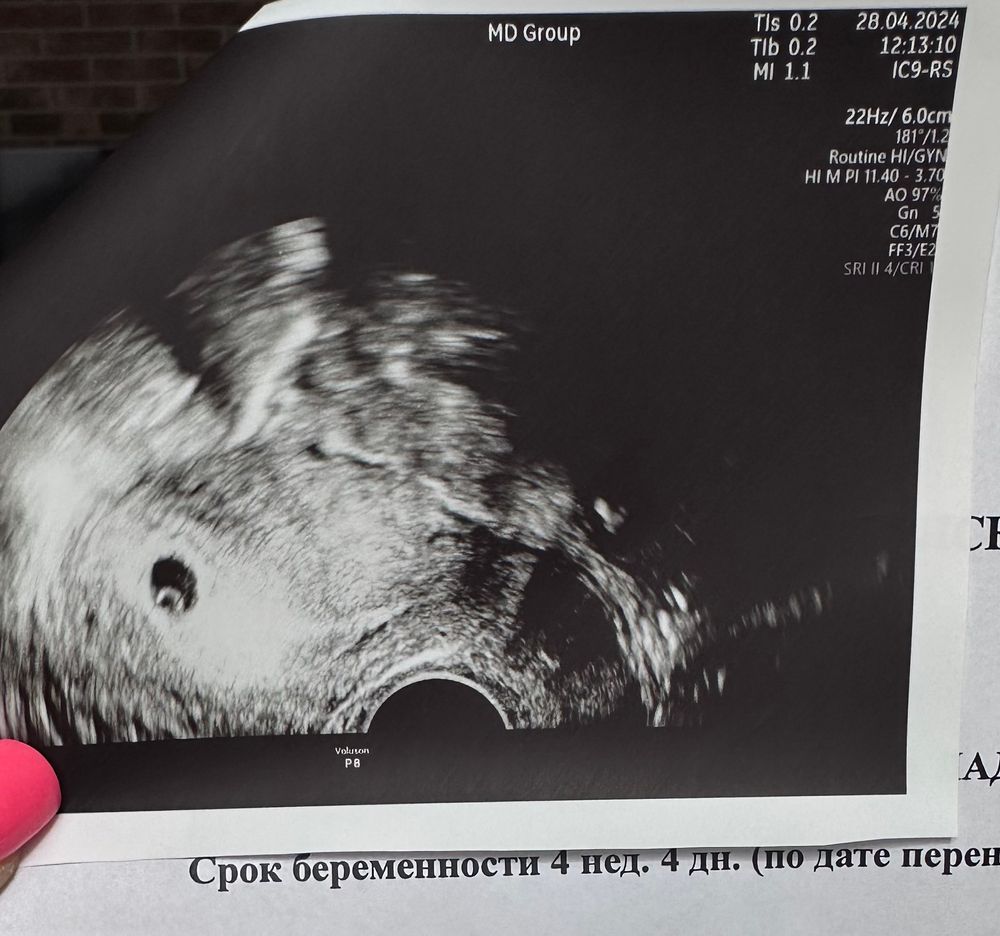

18ДПП и первое УЗИ

Поздравляю, у меня на 19 дпп ПЯ и ЖМ, на 26 дпп эмбрион и сб+. Пусть дальше все будет хорошо, легкой беременности и родов в срок